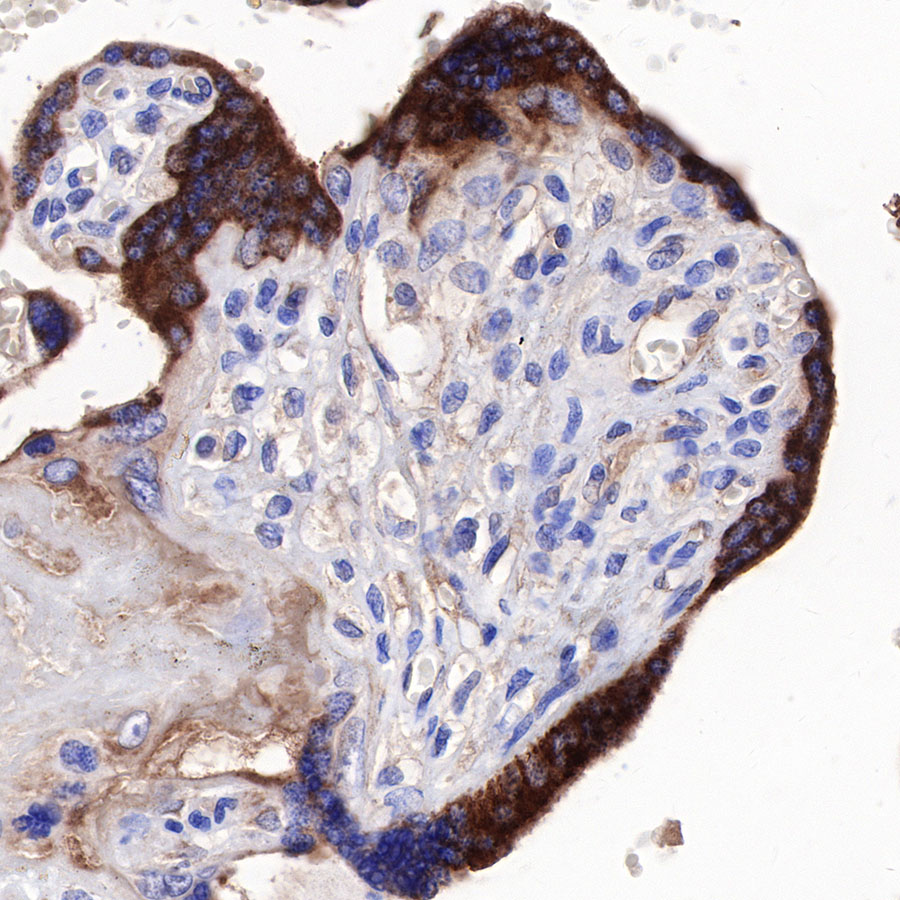

IHC shows positive staining in paraffin-embedded human tonsil. Anti-sFlt-1/VEGF Receptor 1 antibody was used at 1/1000 dilution, followed by a HRP Polymer for Mouse & Rabbit IgG (ready to use). Counterstained with hematoxylin. Heat mediated antigen retrieval with Tris/EDTA buffer pH9.0 was performed before commencing with IHC staining protocol.